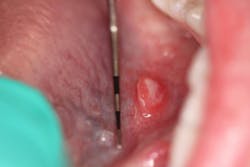

Patient: 71-year-old female

- 5 cm diameter round, greyish-pink mass

- Tissue friable and bleeds easily

- Not tender to palpation

- Located in the right posterior mandible directly behind tooth no. 31